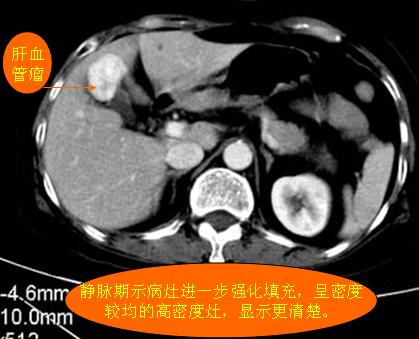

腹部ct解剖与基本病变